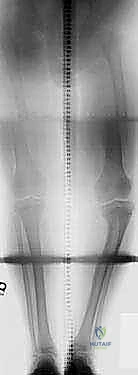

2. التصوير الإشعاعي المتقدم (الأشعة السينية)

تُعد الأشعة السينية الأداة التشخيصية الأهم. يطلب الدكتور هطيف صور أشعة سينية خاصة لكامل الطرف السفلي أثناء الوقوف (Standing long-leg alignment X-rays). هذه الصور ضرورية لـ:

* حساب المحور الميكانيكي (Mechanical Axis): لتحديد مدى انحراف خط الوزن عن مركز الركبة.

* قياس زاوية الظنبوب والفخذ (Tibiofemoral Angle).

* تقييم حالة صفيحة النمو (Physis) ودرجة تعظمها.

* تحديد زاوية التشوه الدقيقة ومكانها (CORA - Center of Rotation of Angulation) للتخطيط الجراحي.